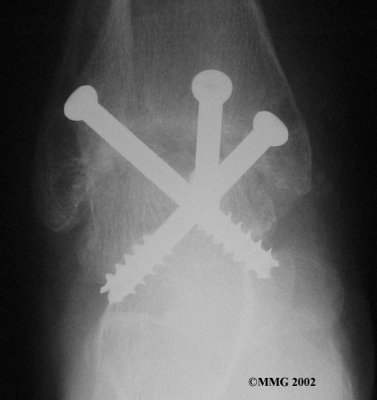

It is important when the surfaces are removed that the angles of the cut surfaces are correct. When the tibia is brought against the talus, the foot should be at a right angle to the lower leg. Once the cuts are made the bones must be held in place while they fuse. This can be done using large metal screws and metal plates if necessary. The screws are usually under the skin and are not removed unless they begin to rub and cause pain.

Inserting the screws

After ankle fusion, the physical therapists at FYZICAL East Louisville can help you learn to walk smoothly and without a limp. Although time needed for recovery varies among patients, an ankle brace will typically replace your cast after eight to 12 weeks. Your surgeon will take X-rays frequently to see if the bones are fusing together. You will probably need to use crutches during the time you wear the cast. As the fusion grows stronger, you will begin to put more weight on your foot when walking.